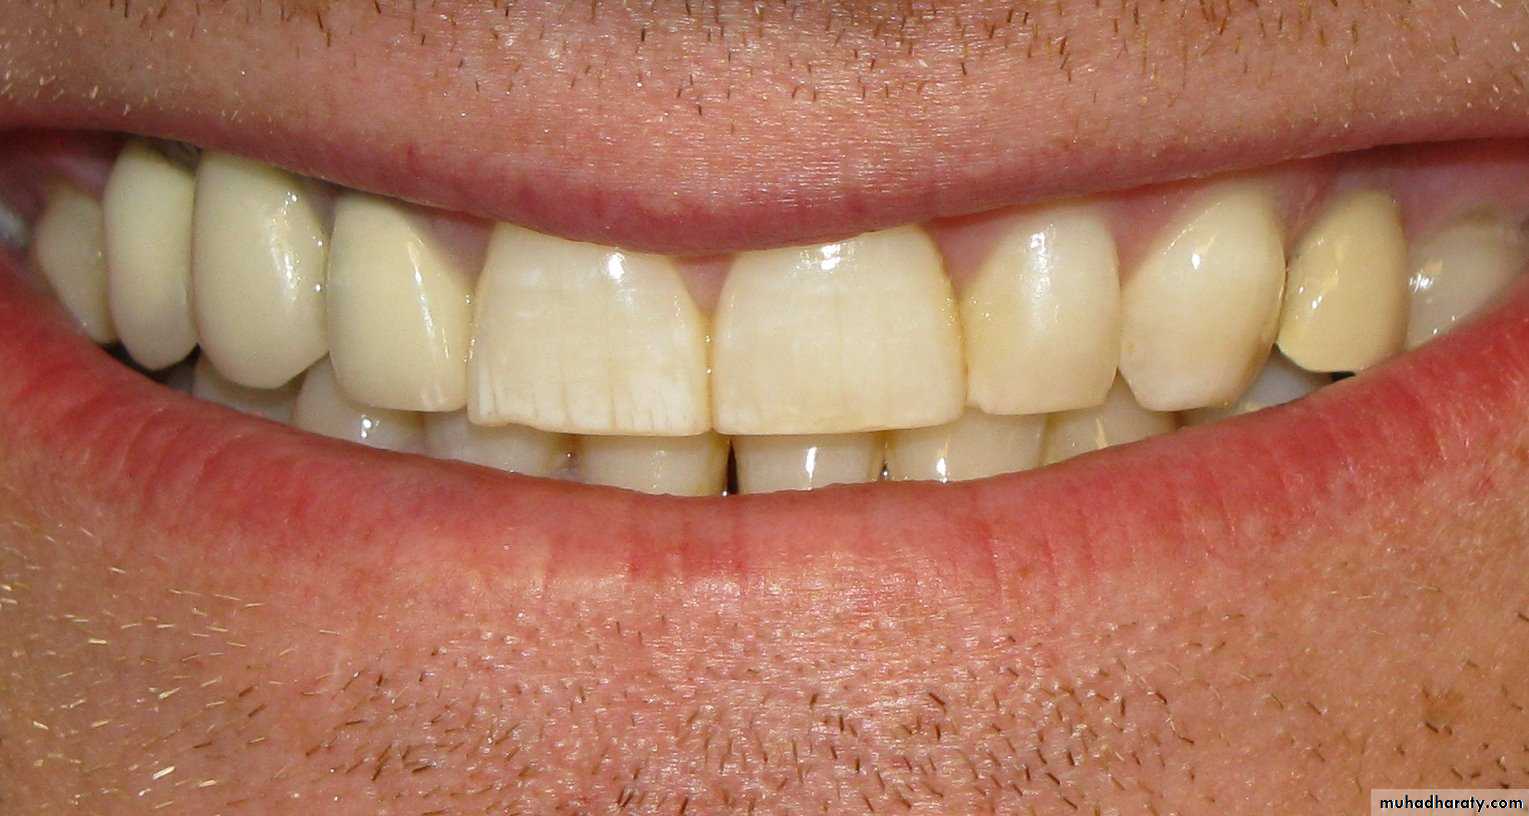

A mild case of dental fluorosis (the white streaks on the subject's upper right central incisor)

Specks / Streaks

Dental fluorosis is a developmental disturbance of dental enamel caused by the consumption of excess fluoride during tooth development